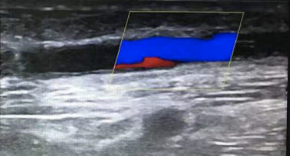

什么是“超声引导下内瘘狭窄球囊扩张术(PTA)”?这是一种在B超引导下,经皮穿刺血管,送入球囊扩张导管,对血管的狭窄部分进行扩张,使狭窄部位矫正至正常血管内径的技术,达到延长患者动静脉内瘘使用寿命的目的。动静脉内瘘在使用过程中随着反复穿刺、内膜增生等因素,内瘘可能出现多种并发症,其中狭窄、血栓是最常见的并发症,可导致内瘘失去功能而无法进行有效透析。这时,拥有微创、无辐射、即时生效等优点的PTA手术就能发挥大功效,只需要在患者皮肤表面穿刺一个2-3毫米大小的穿刺点就能完成手术,创伤面小。而且这个手术可以反复进行,即使经过数月甚至数年的使用再次发生狭窄,也可以再次进行PTA治疗,延长内瘘的寿命。

动静脉内瘘狭窄后,血管较窄,仅有少量血流可以通过。

经球囊扩张术后,狭窄的血管被成功扩开,血管内径增宽,血流量增大。